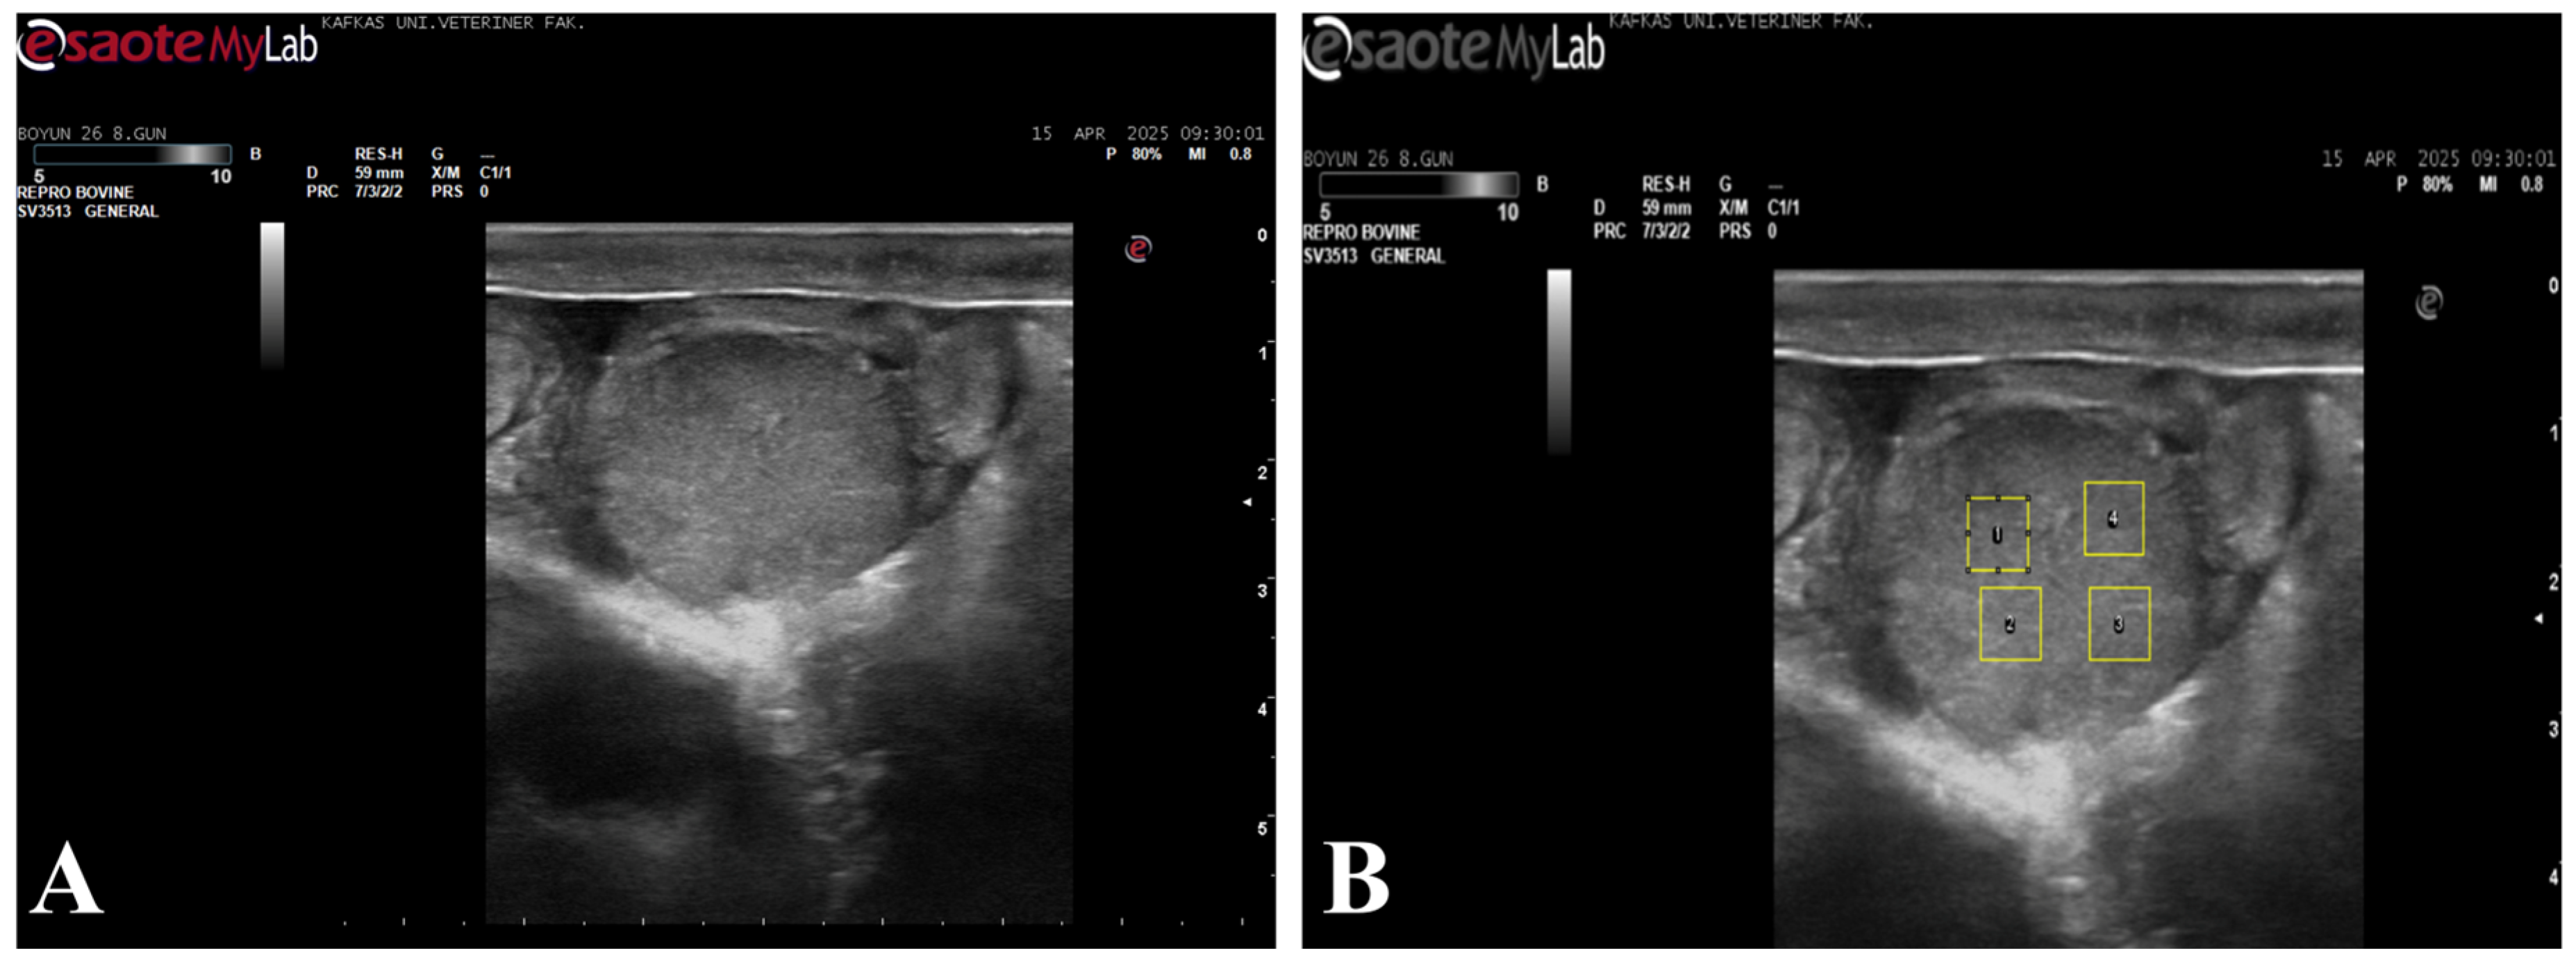

Figure 1.

B-mode ultrasonographic image of the corpus luteum used for echotexture analysis. (A) B-mode ultrasonographic image of the corpus luteum; (B) The same image showing the placement of four regions of interest (ROIs) selected for ImageJ-based grayscale and homogeneity analysis.

2.5. Echotexture Analysis

For echotexture analysis, the recorded images were transferred to a digital environment in bitmap (BMP) format and converted to grayscale prior to analysis. The images were analyzed using ImageJ (v. 1.52, NIH, ABD) software. In each image, four artifact-free regions of interest (ROIs; 35 × 35 pixels) (Figure 1) covering the ovary and endometrium were defined. ROI size was selected in accordance with previously published echotextural analyses employing similar ROI dimensions for standardized image evaluation [12,19]. For corpus luteum analysis, ROIs were placed within homogeneous luteal parenchyma while avoiding cavitations, peripheral borders, and acoustic shadowing artifacts. For uterine assessment, ROIs were positioned within the endometrial layer at comparable anatomical locations, avoiding luminal fluid, folds, and artifacts. ROI placement was performed using consistent anatomical landmarks and standardized image planes to ensure repeatability between examinations. A total of 12 ROIs were evaluated for each animal. Corpus luteum mean gray value (CL-MGV), uterine mean gray value (UT-MGV), as well as corpus luteum homogeneity (CL-HOM) and uterine homogeneity (UT-HOM) parameters, were calculated and used in the statistical analyses. Image analysis and parameter extraction were performed by the same investigator using standardized procedures. Blinding to group allocation was not applied due to the nature of repeated ultrasonographic measurements; however, consistent acquisition settings and predefined analysis protocols were used to minimize potential observer bias.